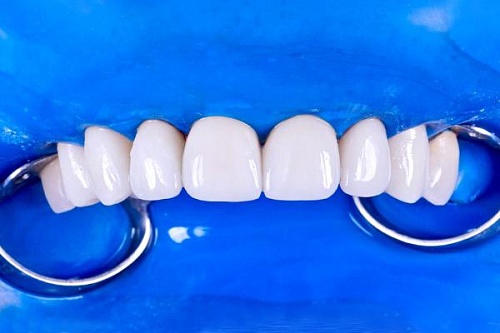

Сохранить зубы и пародонт помогает правильная гигиена полости рта дома и в кресле стоматолога, а также своевременное протезирование и имплантация, которые замещают удаленные зубы и равномерно распределяют жевательную нагрузку, не позволяя костной ткани атрофироваться.